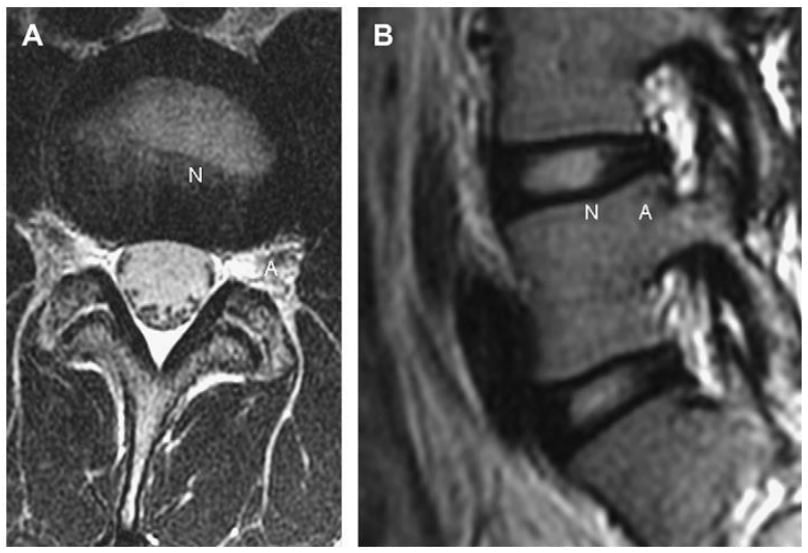

Đĩa đệm bình thường có nhân đĩa bên trong và vòng xơ bên ngoài, và được bao bọc bởi sụn bề mặt thân sống (Hình 1). Nhân đĩa chứa các glycosaminoglycans ái nước với một mạng lưới sợi collagen. Theo thời gian, các lycosaminoglycans gelatin bị thay thế bởi sụn xơ. Vòng xơ gồm 15-20 lá collagen được sắp xếp chéo nhau và yếu nhất ở phía sau ngoài, ở đó các bó collagen được sắp xếp ít hơn. Sụn bề mặt thân sống bao gồm sụn trong, vô mạch và không có thần kinh, được nuôi dưỡng bằng sự khuếch tán từ thân sống và bề mặt thân sống kế cận.

Hình 1. Axial (A) và Sagittal (B) T2W thấy tăng tín hiệu của nhân đĩa bình thường (N) và giảm tín hiệu của vòng xơ bình thường (A).